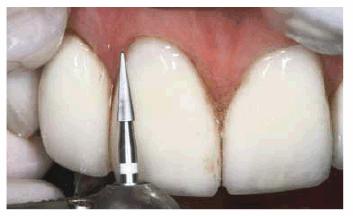

Figure 16-1B: After tooth lightening, the smile is much more pleasing.